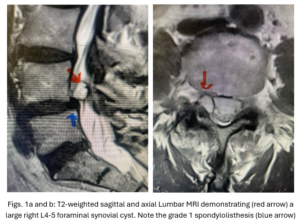

This 54-year-old female with a long history of low back pain presents with three weeks of a progressive right footdrop with associated numbness and tingling of the right leg. In addition, she had right lateral hip pain down to the dorsum of her foot. She first noticed her right foot slapping the floor when she walked. She had no prior trauma or unusual activity before this began. Her chiropractor, who had treated her back pain for a long time, first noticed the foot drop and referred her for further evaluation. She presented with ⅖ strength in her right dorsiflexor. MRI revealed a large right L4-5 foraminal synovial cyst with some mass-effect on the thecal sac. (Fig. 1) She also had an associated grade 1 spondylolisthesis. Because the cyst was more foraminally-oriented, it had the majority of its effect on the right L4 nerve root. It was felt the patient required surgery to attempt to reverse her weakness. We performed a decompressive laminectomy at L4, removing the inferior facet process on the right in order to gain lateral and foraminal access to the right L4 nerve root. In the lateral recess there was a heap of inflammatory tissue which we entered, revealing the cyst. The medial wall was stuck to the dura. We internally decompressed the cyst which was mainly gelatinous material with some fluid. We dissected and removed as much of the cyst we could safely remove but left the medial wall for fear of removing it would cause a CSF leak, upon removing the bulk of the cyst we encountered anteriorly the descending and exiting right L4 nerve root which was purplish in color and clearly inflamed. We performed a generous foraminotomy of the right L4 as well as the right L5 nerve root. We also performed an instrumented fusion at L4-5 (Fig. 2).

This 50-year-old female with a long history of low back pain and a prior history of multiple lumbar surgeries with instrumentation. She had a L3-5 laminectomy with instrumentation about 7 years prior and now presents with progressive worsening of low back pain. The pain was worse with activity, standing, walking, and prolonged sitting. She had an MRI which showed next segment degeneration at L2-3 with stenosis and the development of a large posteriorly-oriented synovial cyst with thecal sac compression (Fig. 3). The patient failed all means of conservative management including physical therapy and epidurals. We decided to perform an L revision laminectomy to decompress and remove the cyst as well as explore her prior fusion. In this case, again the anterior wall of the sac was completely stuck to the dural membrane. Therefore, we internally decompressed the cyst which was mainly degenerated, necrotic material and removed as much wall of the cyst that could be safely removed. There was some fluid within the cyst. Of note during the dissection of these cysts there is often a release of cyst fluid the patient was well-decompressed. We removed the prior instrumentation and added a new L2-3 construct (Fig. 4). The patient had an uneventful hospital course and was discharged on post op day 2.